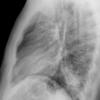

Case 2  Lingular pneum Lat

Date: 04/17/2005

Views: 6960